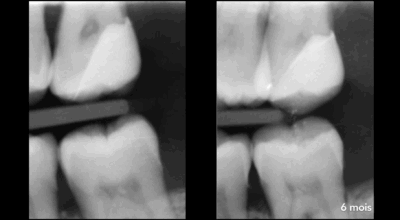

Cas clinique d’une 17 (2e molaire en haut à droite)

Coiffage pulpaire indirect : 96,4% de taux de succès